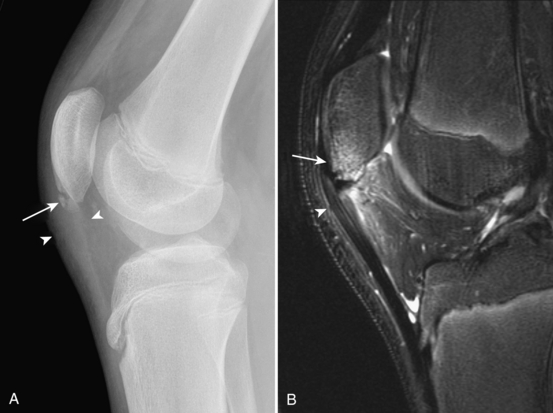

Ларсена йохансона

Ларсена йохансона 146 фото